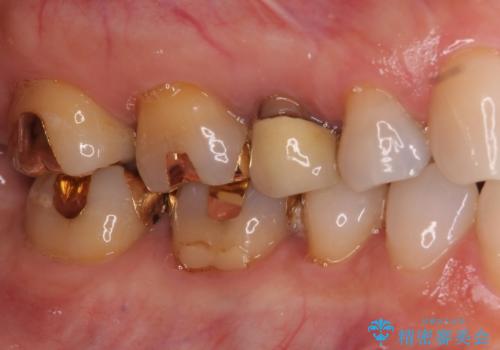

- 歯肉が退縮したためにクラウンの縁や歯根が見えてしまっていることを気にして来院された患者様です。

また、歯肉が黒く変色していることも気になるとのことでした。

仮歯に変える際に歯肉の一部を切除し、金属片による変色を除去した後、オールセラミッククラウンにて補綴することとしました。

メタルタトゥー(金属イオンの溶出による歯肉の変色)は、歯に装着された金属から金属イオンが溶け出したり、金属を除去するときの切削片が歯肉に入り込んでしまったりして引き起こされます。

物理的に除去をすることできれいな歯肉となりますが、残留している金属イオンにより再発するリスクがあります。